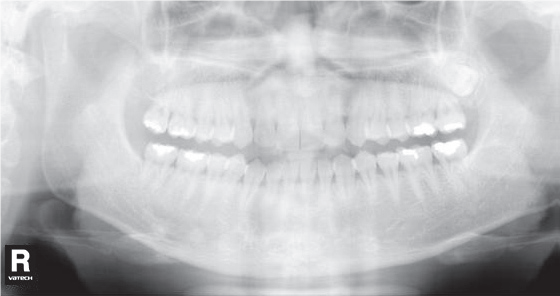

1. Суммация тени позвоночника на резцы и клыки обеих челюстей, в виде наложения белых полупрозрачных теней в середине снимка.

Рис. 1. Наложение темной тени на верхушки зубов верхней челюсти.

Одна из самых частых ошибок на снимках. Связана с положением шейного отдела позвоночника у пациента во время сканирования.

Что делать:

- Попросите пациента выпрямить шейный отдел позвоночника